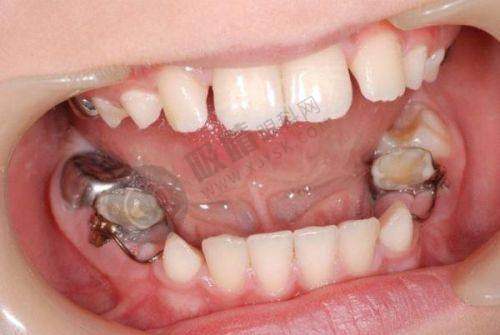

在了解福州美可普口腔预约方式之前,先为大家介绍一下相关的口腔项目信息。此次涉及的口腔项目为口腔外科,参考金额约为300元,预计修复时间大概是90天。福州美可普口腔凭借其广泛的布局和专精的医疗团队,在福建省口腔医疗领域占据着重要地位。它的各个分院分布在不同城区,方便周边居民就诊。而本文的目的就是要让大家清楚地知道如何通过多种方式预约福州美可普口腔的诊疗服务。除了下面要介绍的具体预约方式外,大家还可以通过该平台进行预约。只需向客服留下个人需求和联系方式,之后等待客服发送预约成功的信息即可。